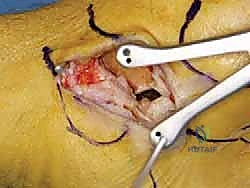

الخطوة الثالثة: الشق الجراحي والوصول الآمن

يتم عمل شق جراحي دقيق ومدروس على الجانب الداخلي للكاحل، خلف وتحت الكعب الإنسي. يستخدم الدكتور هطيف تقنيات تشريحية دقيقة لحماية الهياكل الحيوية المحيطة، وخاصة العصب الصافن (Saphenous Nerve) والوريد المرافق له، لتجنب أي تنميل أو ألم عصبي مزمن بعد الجراحة.

الخطوة الرابعة: تقييم وإصلاح رباط الدالية (Repair vs. Reconstruction)

بمجرد الوصول إلى رباط الدالية، يتم تقييم درجة التلف:

* الإصلاح المباشر (Direct Repair): إذا كانت أنسجة الرباط الممزقة ذات جودة جيدة (عادة في الإصابات الحديثة)، يقوم الدكتور هطيف بخياطتها مباشرة. يستخدم خطاطيف تثبيت عظمية (Suture Anchors) صغيرة جداً ومصنوعة من مواد متوافقة حيوياً (تذوب مع الوقت أو من التيتانيوم) لغرس الخيوط القوية في عظمة الكعب الإنسي، ثم يتم سحب الرباط الممزق وتثبيته بقوة في مكانه التشريحي الأصلي.

- إعادة البناء (Reconstruction): في الحالات المزمنة حيث يكون الرباط الأصلي قد تليف، تآكل، أو أصبح غير كافٍ للاستخدام، يلجأ الدكتور هطيف إلى تقنية "إعادة البناء". تتضمن هذه التقنية المتقدمة استخدام رقعة وترية (Graft)، إما من جسم المريض نفسه (Autograft - مثل أوتار الركبة أو وتر من القدم) أو رقعة صناعية متطورة. يتم حفر أنفاق ع